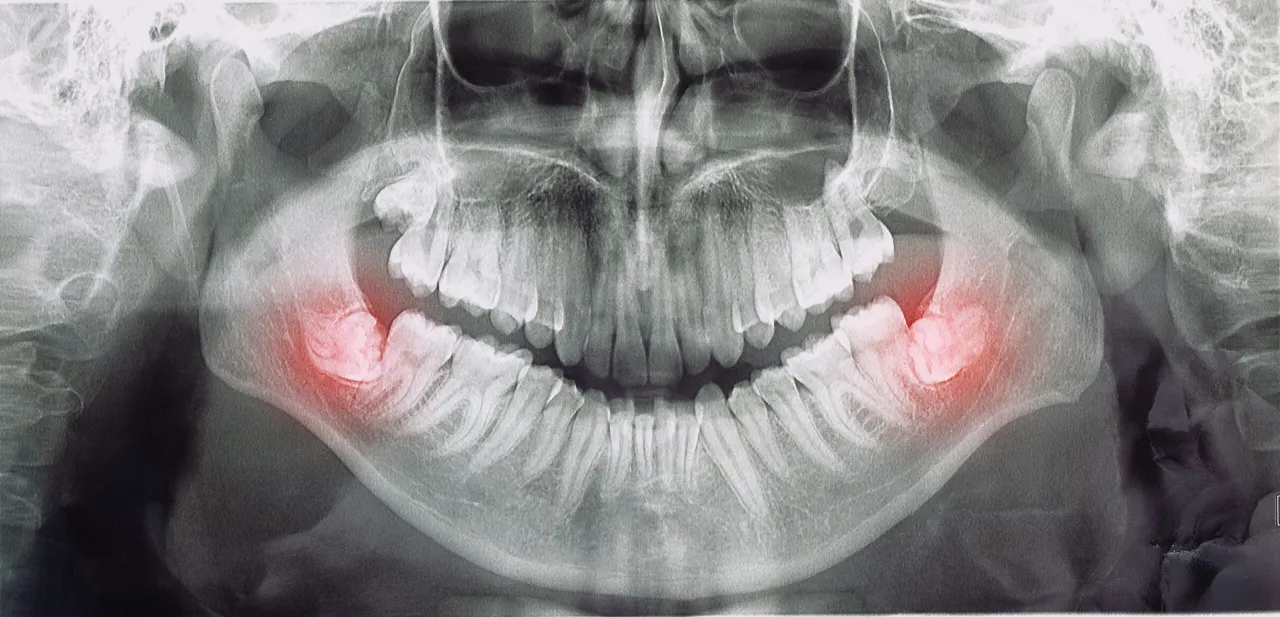

- Diagnostyka obrazowa: Zazwyczaj konieczne jest wykonanie zdjęcia rentgenowskiego (np. pantomogramu lub zdjęcia punktowego), aby ocenić stan korzeni zębów, obecność ropni, stan zębów mądrości czy zmiany w kości.

- Leczenie kanałowe: Jeśli przyczyną jest martwica miazgi lub ropień, konieczne może być leczenie kanałowe zęba, polegające na usunięciu zainfekowanej tkanki i wypełnieniu kanałów.

- Ekstrakcja zęba: W niektórych przypadkach, zwłaszcza przy zębach mądrości, które nie mogą prawidłowo się wyrznąć lub są źródłem przewlekłych infekcji, konieczne może być usunięcie zęba.

- Nacięcie i drenaż ropnia: Jeśli powstał ropień, stomatolog może naciąć go, aby umożliwić odpływ ropy i zmniejszyć ciśnienie.